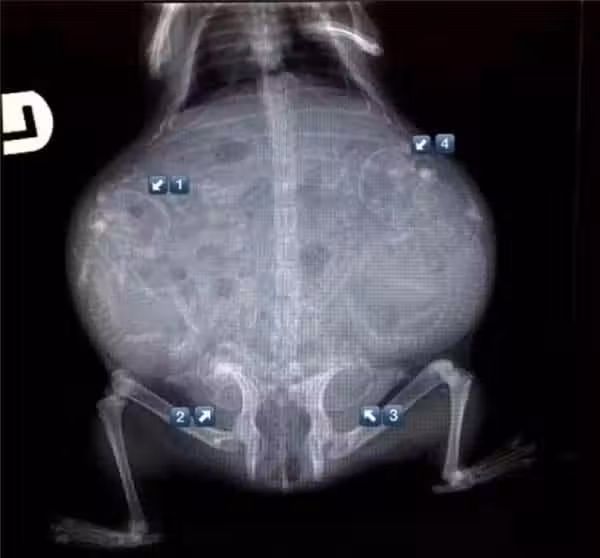

17張你沒看過的動物懷孕照,看了「母鯊魚的肚子」整個人都不好了

17.雪貂媽媽,雖然不是X光但也一樣驚人